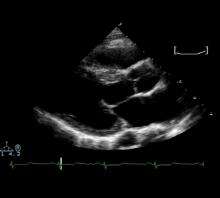

Systolic anterior motion of the mitral valve

![]() Echocardiogram demonstrating systolic anterior motion of the anterior leaflet of the mitral valve |

Dynamic outflow obstruction (when present in HCM) is usually due to systolic anterior motion (SAM) of the anterior leaflet of the mitral valve. Systolic anterior motion of the mitral valve was initially thought to be due to the septal subaortic bulge, narrowing the outflow tract, causing high-velocity flow and a Venturi effect—a local underpressure in the outflow tract. Low pressure was thought to suck the mitral valve anteriorly into the septum. But SAM onset is observed to be a low-velocity phenomenon: SAM begins at velocities no different from those measured in normal hearts.[16][17] Hence, the magnitude and importance of Venturi forces in the outflow tract are much less than previously thought, and Venturi forces cannot be the main force that initiates SAM.